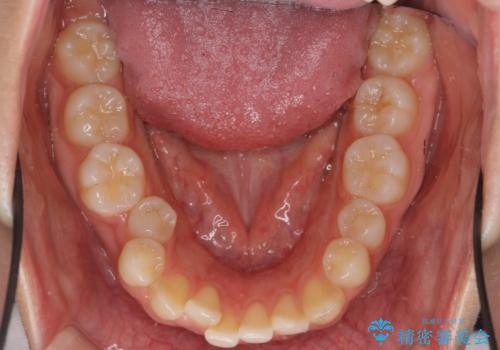

- 歯並びが気になるとのことで来院。

前歯、奥歯ともに反対咬合になっており、また上顎の前歯が少し突出気味でした。

上下左右の小臼歯を抜歯しています。